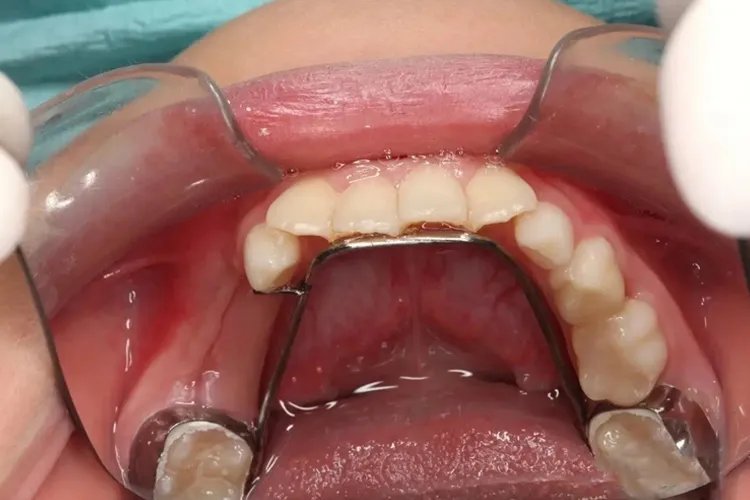

固定舌弓式此种类型的乳牙间隙保持器,常用于下颌乳尖牙早失,在下颌第一磨牙做带环附固定舌弓,以维持下颌牙弓长度,在舌弓上焊阻挡丝维持下颌切牙与第一乳磨牙位置,使之不向缺隙移动。